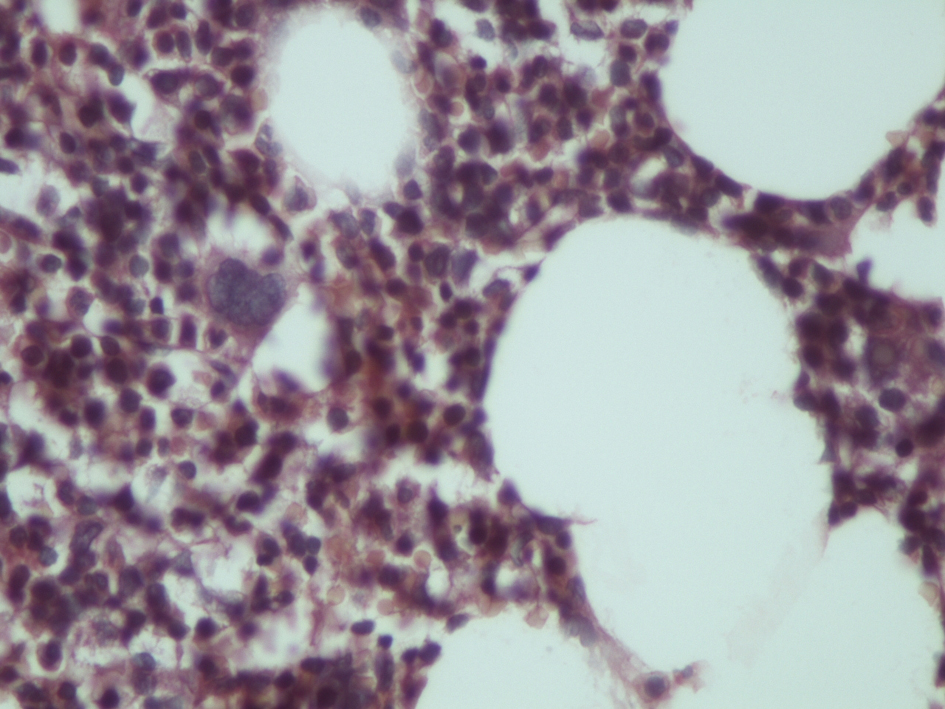

Myelolipomas are well circumscribed in gross inspection, but are rarely encapsulated. Their color varies from pale yellow to deep red or brown depending upon the relative proportion of fat and hematopoietic elements. The contour of the adrenal myelolipoma is smooth, wavy, or irregular and may shoe intermingling of cortical cells with elements of the myelolipoma. The surrounding cortical cells can be relatively normal in appearance or compressed (Fig. 1). There is a variable mixture of mature fat with hematopoietic elements, often with full representation of the major cell lines (Fig. 2). Rarely foci of ossification are seen.

![]() Click for large image | Figure 2. Histological section of myelolipoma indicating haemopoetic elements and lipocytes (hematoxylin-eosin × 240). |